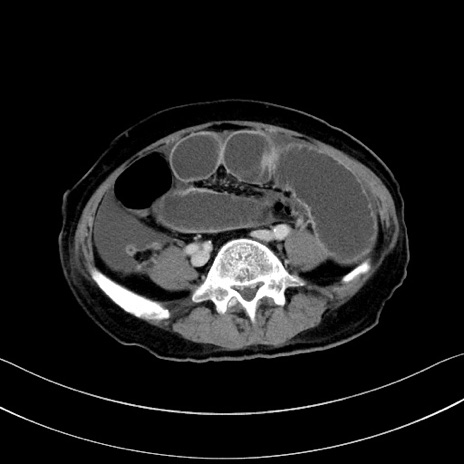

症例28(横断像)

【症例】60歳代男性

【主訴】嘔吐

【現病歴】胃癌にて胃全摘後。食思不振が悪化し、夜中に嘔吐することがある。

【既往歴】胃癌、胃全摘、脾摘、胆摘後

【データ】WBC 5900、CRP 10.56